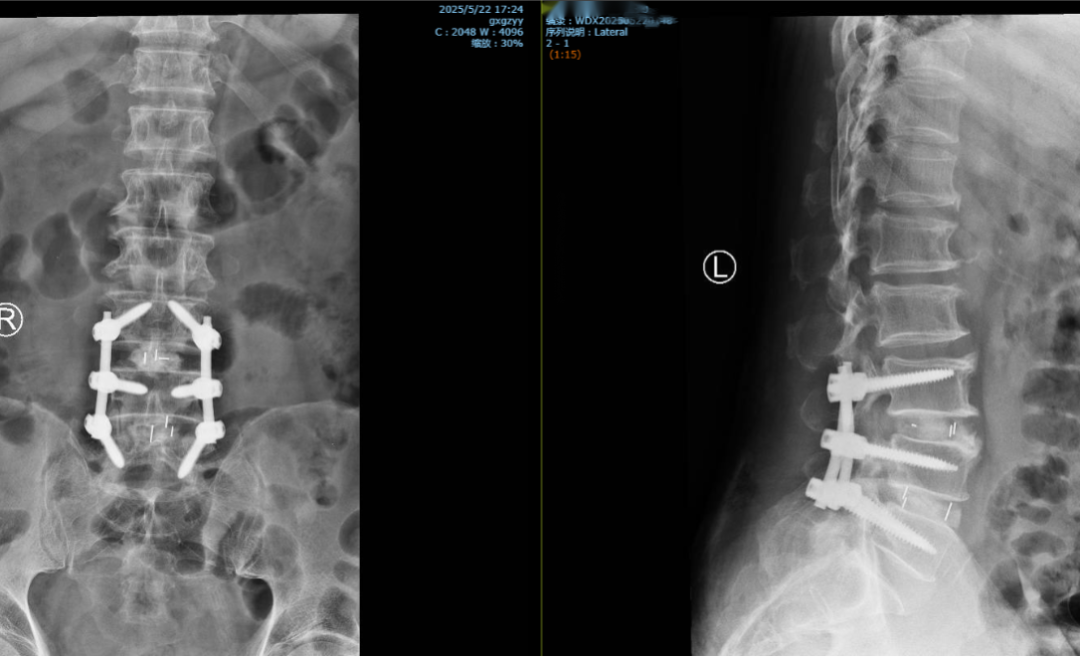

“患者病情非常复杂。”彭小忠说,患者有冠心病史致心功能储备不足,高血压病史则增加了术中出血风险,而脑梗病史则要求麻醉及术后管理需高度谨慎。针对患者的身体情况,团队联合心脏中心、神经内科、麻醉科、眼科等进行多学科会诊,为其制定个性化手术方案,最终决定采用“L3/4、L4/5微创通道下腰椎后柱融合术”。

据介绍,该技术采用后路肌间隙微创4.5cm切口,精准分离,术中运用神经电生理监测,实时保护神经功能,术后第一天患者症状显著好转,住院5天便开心出院,家属对医院精湛的医术大为赞叹,欣喜之余特意送来锦旗致谢。

彭小忠(右图右一)为患者Quandrant通道下行L3/4、L4/5Mis-TLIF手术